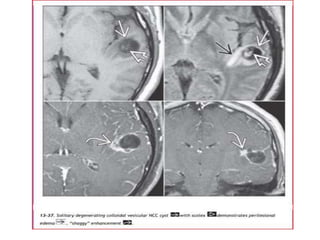

Vesicular Stage

• Cyst with dot sign

• CSF density/intensity

• No enhancement is typical, although very faint enhancement of the

wall and enhancement of the scolex may be seen.

Colloidal vesicular

• Cyst fluid becomes turbid

– CT: hyperattenuating to CSF

– MRI T1: hyperintense to CSF

• Surrounding oedema

• Cyst and the wall become thickened and brightly enhances

• Scolex can often still be seen as an eccentric focus of enhancement

Cyst fluid is hyperdense relative to CSF on NECT and

demonstrates a ring enhancing capsule on CECT

Vesicular Stage • Cystwith dot sign • CSF density/intensity • No enhancement is typical, although very faint enhancement of the wall and enhancement of the scolex may be seen.

Colloidal vesicular • Cystfluid becomes turbid – CT: hyperattenuating to CSF – MRI T1: hyperintense to CSF • Surrounding oedema • Cyst and the wall become thickened and brightly enhances • Scolex can often still be seen as an eccentric focus of enhancement

Cyst fluid ishyperdense relative to CSF on NECT and demonstrates a ring enhancing capsule on CECT